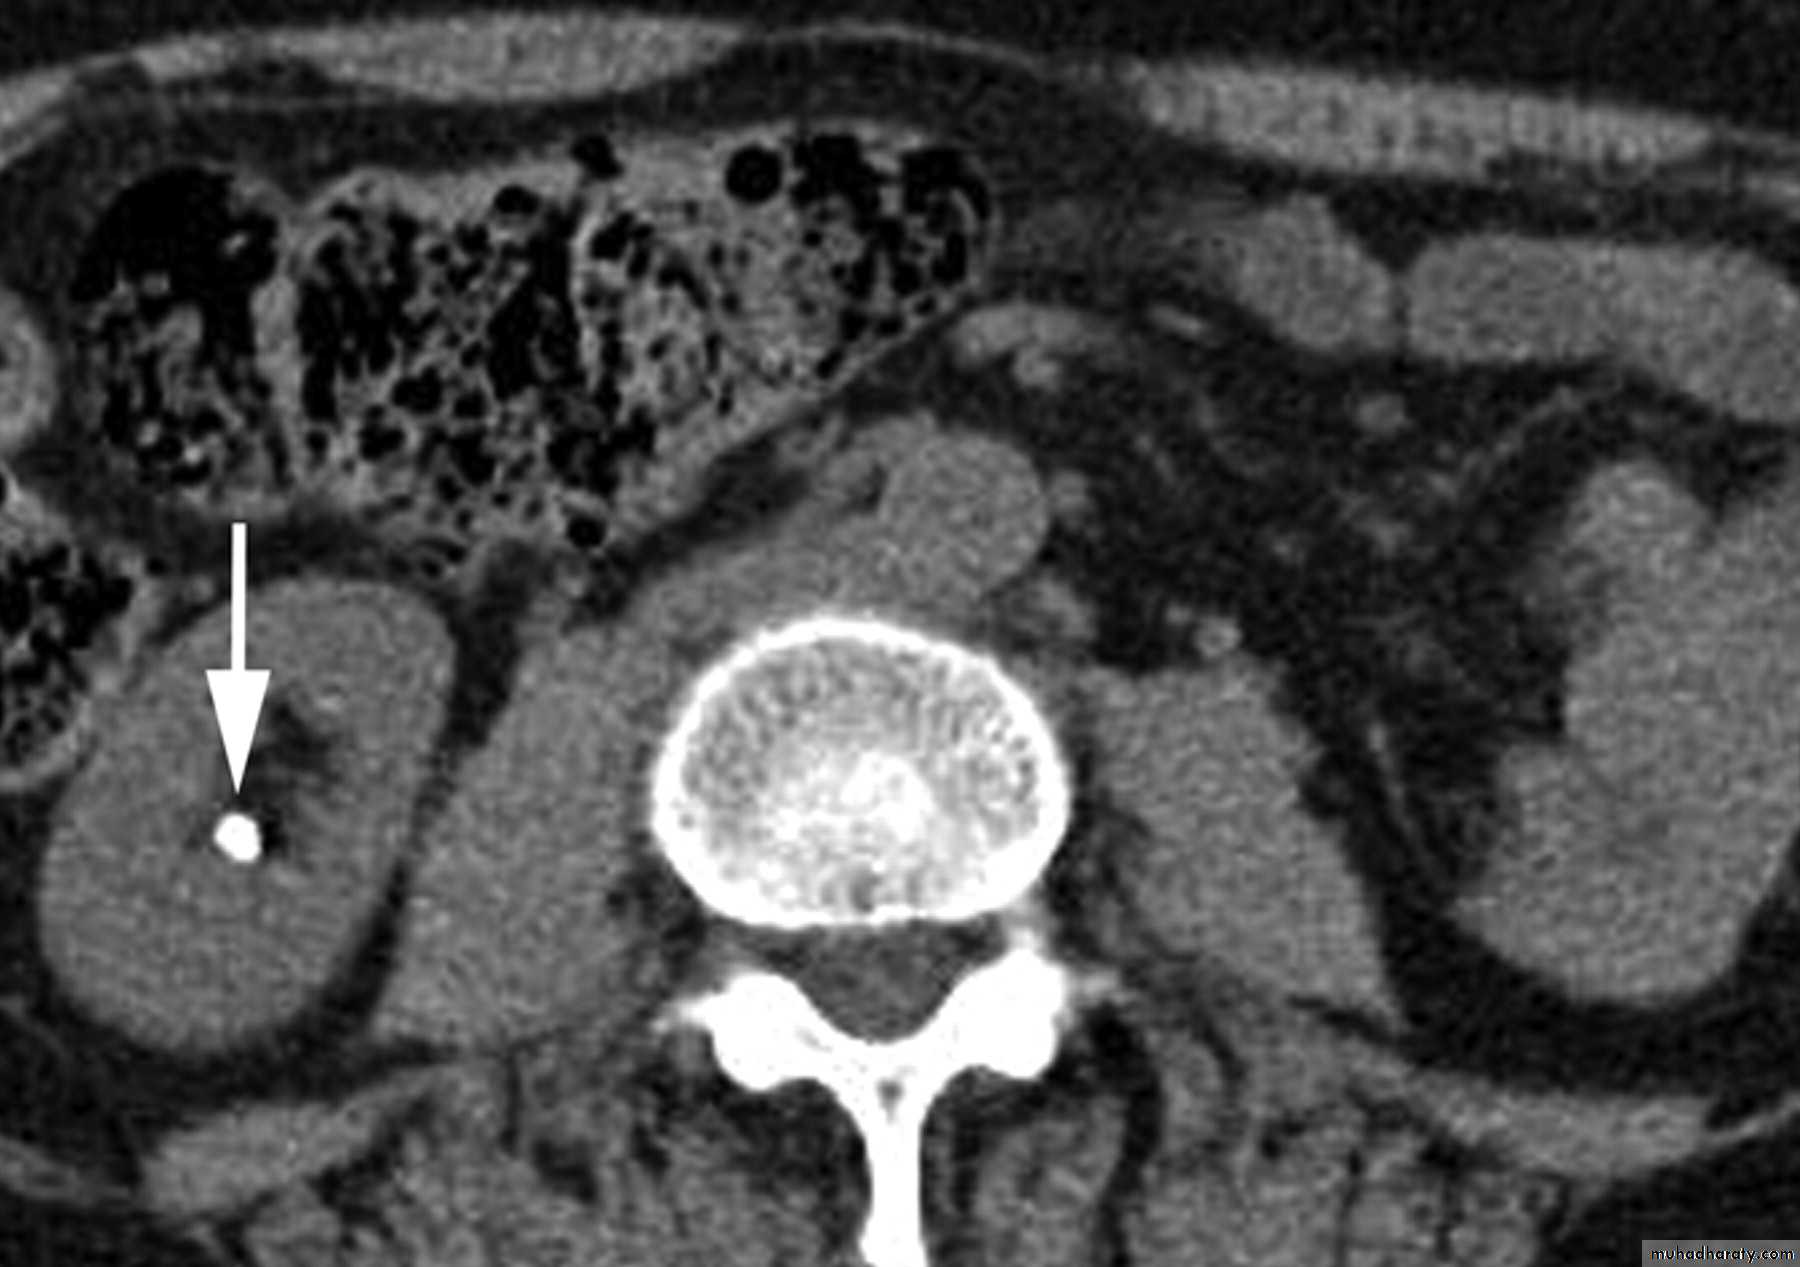

CT scans used in some hospitals during acute renal stone-Non contrast CT sensitively identify calculi and non opacified collecting system down to the level of obstruction. it has a sensitivity of 97% and specificity of 96% for detection of ureteral calculi

- Over 90% of calculi are radiopaque on plain films and virtually all on CT as very sensitive for detection of calculi, even those that appear radiolucent on plain film.- Most of these stones are a mixture of calcium oxalate and phosphate.

- Only pure uric acid and xanthine stones are radiolucent on plain x-ray but CAN be identified by CT or US , uric acid stones are associated with increased uric acid excretion in urine as in gout.